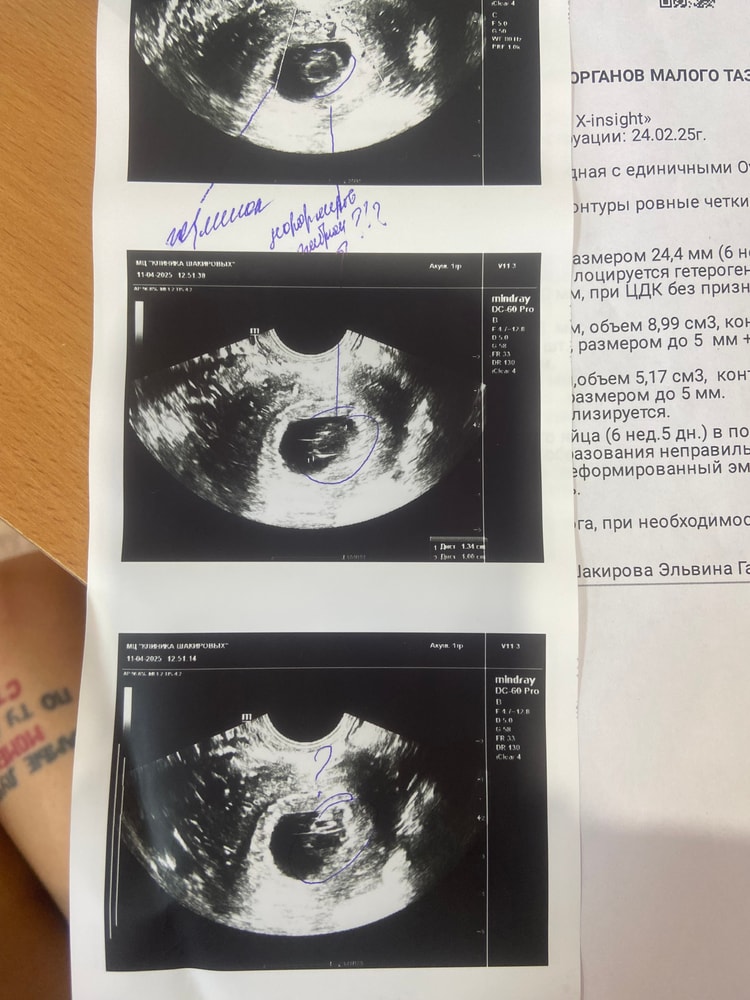

Марина, вот 7 апреля на первом узи у меня пя 12,98mm. И 11 марта я была на втором узи, я у узиста спросила, мне ставят срок 6 недель, это акушерские? Она мне ответила, что нет эмбриональные. Уже не знаю кого слушать и что делать

У меня в феврале была похожая история, ждала до 8-9 недель, но положили в больницу под наблюдение пролежала до ПЯ 28,8мм тм стал уменьшатся 1,8 мм а по первом узи 2,5мм потом 2 мм, подписала согласие на вакуум, так как самой стало видно что уже ждать бессмысленно, попробуйте уговорить врача положить под наблюдение так как сроки позволяют, хгч неинформативно уже, у меня отлично рос как обычная Б, но с первого узи ставили под вопросом, и так все 4 узи подтверждали анэмбрионию, не теряйте надежду но готовьтесь к худшему что бы быть готовой к любому исходу. Первое узи пя 9,3 мм жм 2,5мм 4459хгч Второе узи пя 21мм жм 2,5мм 8135хгч (в платной клинике ) Третье узи пя 25мм жм 2мм Четвертое узи пя 28,8 жм 1,8мм подтвердили Анэмбрионию подпись на вакуум хгч 18709 ( в стационаре )

Я бы переделала узи, раз рост хгч такой шикарный и такие данные узи, действительно пугает что нашли еще что-то, КРОМЕ эмбриона и жм , +25мм пустое пя тоже вызывает сомнения

hsnvnst, жм есть

Диана Ноилес, да, я вижу. Жм вообще до 15мм пя появляется, а эмбрион ждут до 25мм. У вас уже срок поджимает(

Не хочу пугать, но учитывая что в плодном яйце врач видит что-то странное без кровотока и учитывая какой у вас быстрый рост ХГЧ при отсутствии эмбриона, то пузырный занос может быть вариантом тоже. В любом случае, идите к хорошему УЗИсту. Удачи!

Если сомневаетесь, сделайте через неделю, 1,5 ещё раз узи.. Может сердцебиение появится.. Хотя если деформированный эмбрион... (1ый раз о таком слышу если честно), Хотя тут не знаешь что вам посоветовать... Наверное всё таки слушать врачей.. Я бы через неделю сделала узи и там решала...